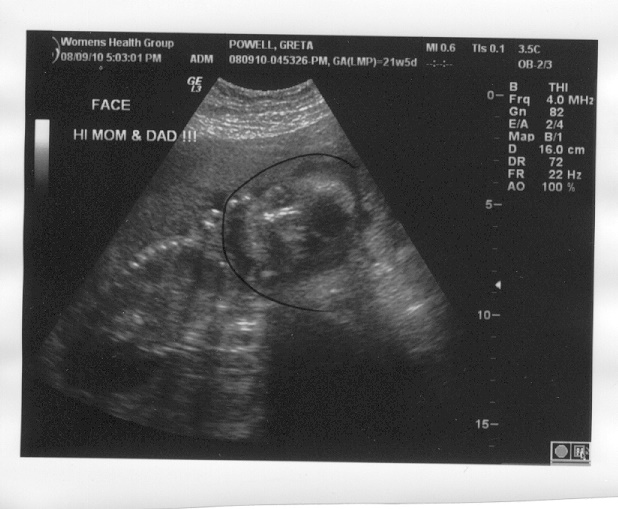

Adventures in Baby Making 16 Weeks Ultrasound Pics